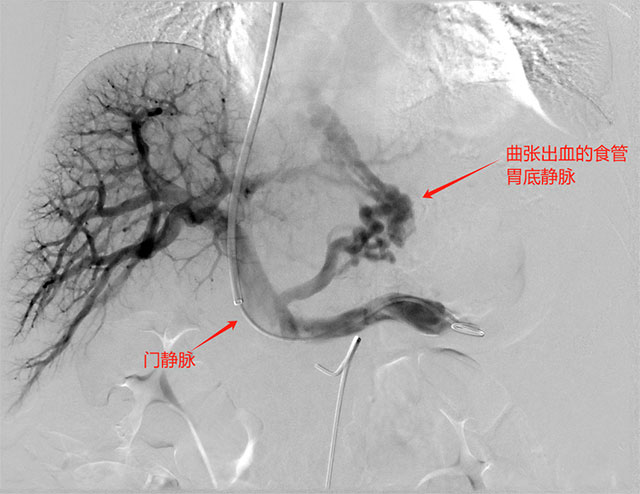

经颈静脉肝内门腔静脉分流术是外周介入中最难和风险最大的技术,是近20年发展起来的一项介入放射学治疗技术。简而言之,就是通过微创技术,栓塞出血的食管胃底曲张静脉,称之为“堵”,然后在门静脉与肝静脉支架建立一个通道,降低门静脉压力,类似于水利工程中的泄洪,称之为“疏”。疏堵并重,双管齐下,打通患者生命通道。

△术中门静脉造影提示,食管胃底静脉重度迂曲、扩张

完善急诊术前准备后,徐燕能博士以颈内静脉为穿刺入口,将导管经上腔静脉、右心房、下腔静脉,插入肝静脉并在DSA设备的引导下由肝静脉穿刺进入门静脉内,然后扩张两者间肝实质通道后,扩张后植入专用TIPS支架在肝静脉与门静脉之间建立人工分流通道,使门静脉血流直接分流到下腔静脉,从而降低门静脉压力,达到治疗静脉曲张破裂出血、顽固性腹水等门静脉高压症的目的。